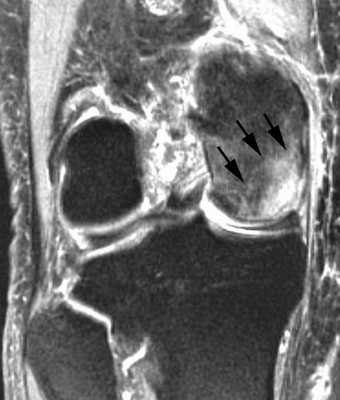

Диагностирование заболевания на ранних этапах проводится при помощи МРТ.

МРТ (магнитно-резонансная томография). Данная диагностическая методика позволяет обнаружить патологии, не отображаемые на рентгеновских снимках и/или не имеющие тех или иных симптомов. Благодаря такой важной особенности, МРТ считается более предпочтительным вариантом диагностирования остеонекроза.